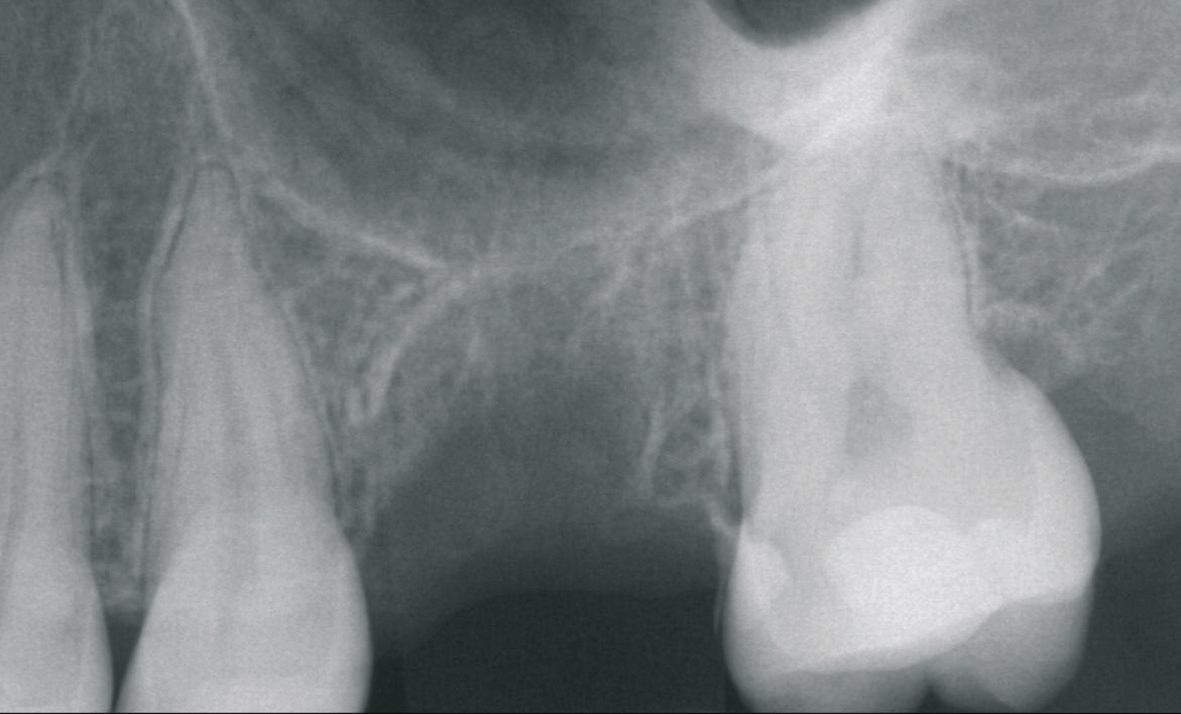

Eine der häufigsten Indikationen für Implantate überhaupt stellt die Einzelzahnlücke nach Verlust eines ersten Molaren dar. Bei den meisten Fällen liegt ein stabiles vertikales Knochenangebot an den Nachbarzähne vor, sodass in der Regel nach Ausheilung des apikalen Granulationsgewebes von einer guten Knochenregeneration auszugehen ist, so dass keine Notwendigkeit der Insertion von kurzen oder ultrakurzen Implantaten gegeben ist. Im Oberkiefer kann bei einer weiten Divergenz der Wurzeln des extrahierten Zahnes es zu einer ausgeprägten Pneumatisation der Kieferhöhle kommen. Daher werden gerade beim jugendlichen Patienten dort dann kurze Implantate eingesetzt, um auf eine Sinusbodenelevation mit einem lateralen Zugang verzichten zu können [3]. Die Implantate können mit oder ohne eine Navigationsschablone gesetzt werden [4]. Da die Lücke begrenzende Nachbarzähne eine gute Orientierung in der mesio-distalen Dimension ermöglichen, kann oftmals auch auf eine Orientierungsschablone verzichtet werden. In der oro-vestibulären Richtung muss der Anwendung des größeren Durchmessers Rechnung getragen werden. Dies kann mit einfachen Positionierungshilfen erfolgen, damit die Implantatachse möglichst zentral in der Kaufläche zu liegen kommt (Abb. 1-8). Die Einzelzahnlücke kann mit einer integrierten verschraubbaren Abutment-Hybrid-Krone oder mit einem Abutment und einer zementierten Krone versorgt werden [5].